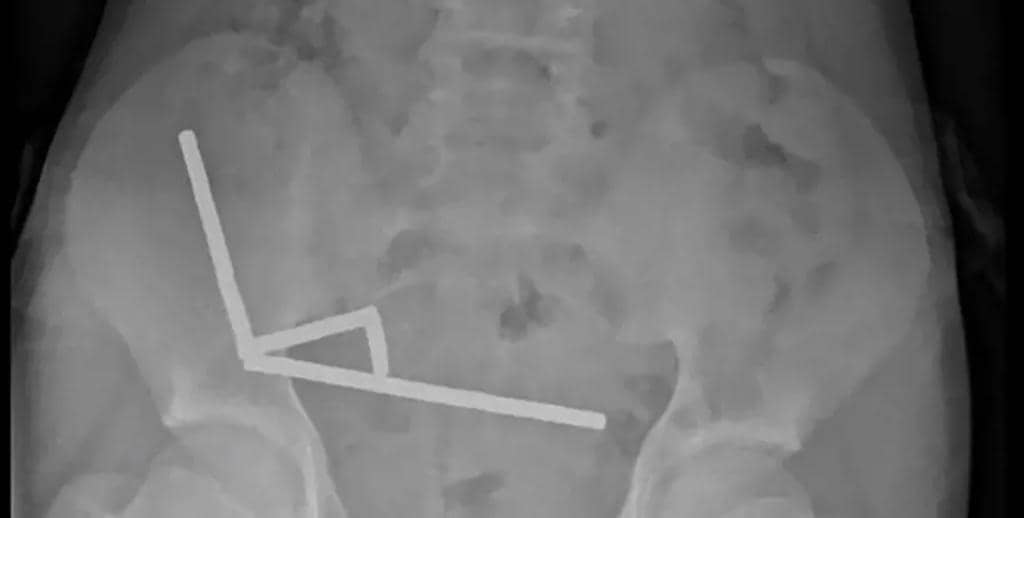

ابتلع مراهق عمره 13 عاما نحو 100 مغناطيس اشتراه عبر الإنترنت، مما أجبر الجراحين في نيوزيلندا على إزالة أنسجة تالفة من أمعائه. وبعد معاناته آلاما في البطن استمرت 4 أيام، نقل إلى مستشفى تاورانغا في الجزيرة الشمالية لنيوزيلندا. وجاء في تقرير صادر عن أطباء المستشفى في المجلة الطبية النيوزيلندية: “أكد أنه ابتلع ما يقرب من 80 إلى 100 مغناطيس قبل نحو أسبوع”. وأضاف الأطباء أن المغناطيسات، التي حظرت في نيوزيلندا منذ كانون الثاني/ يناير 2013، تم شراؤها من منصة التسوق الإلكترونية “تيمو”. وأظهرت الأشعة أن المغناطيسات تكتلت معاً في 4 خطوط مستقيمة داخل أمعاء المراهق، و”يبدو أنها كانت في أجزاء منفصلة من الأمعاء ملتصقة ببعضها البعض بسبب القوى المغناطيسية”، وفق الأطباء. وأكد الأطباء أن ضغط المغناطيس تسبب في موت أنسجة في أجزاء من الأمعاء الدقيقة والغليظة. وأجرى الجراحون عملية جراحية لإزالة الأنسجة الميتة وإخراج القطع المغناطيسية، وتمكن الطفل من العودة إلى المنزل بعد أن قضى 8 أيام في المستشفى. وحذر الأطباء من أن جراحة ابتلاع المغناطيس يمكن أن تؤدي إلى مضاعفات لاحقة في الحياة، مثل انسداد الأمعاء وفتق البطن والألم المزمن.  رد فعل “تيمو”قالت “تيمو” إنها بدأت تحقيقاً لضمان امتثالها لمتطلبات السلامة في نيوزيلندا. وأعربت الشركة الصينية عن أسفها لسماع الخبر، وقال متحدث باسمها في بيان: “أجرينا مراجعة داخلية وتواصلنا مع المجلة الطبية النيوزيلندية للحصول على مزيد من التفاصيل حول الحالة”. وتابع المتحدث: “في هذه المرحلة لم نتمكن من تأكيد ما إذا كانت المغناطيسات المعنية تم شراؤها عبر تيمو، ومع ذلك تراجع فرقنا القوائم ذات الصلة لضمان الامتثال الكامل لمتطلبات السلامة المحلية”. وتعرضت “تيمو” لانتقادات في أسواق عدة، بسبب “عدم بذلها جهوداً كافية للتخلص من المنتجات غير القانونية من منصتها”.